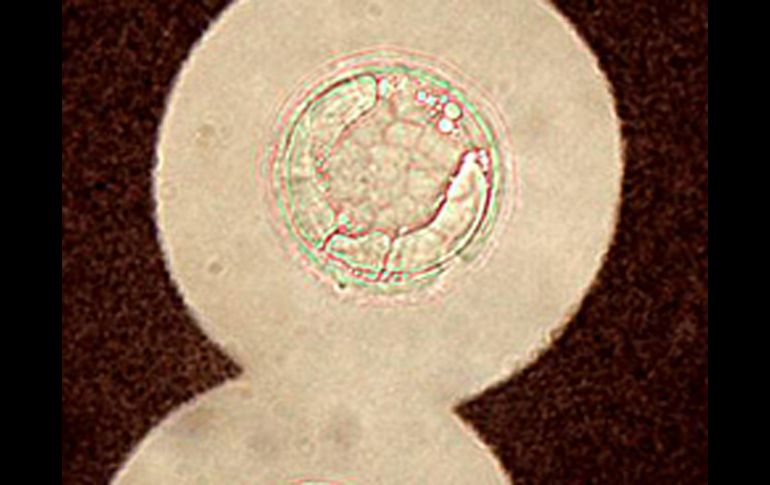

Imagen del hongo 'Cryptococcus neoformans'. EL MUNDO.ES  /

El hongo, denominado 'Cryptococcus neoformans', es una levadura que se encuentra en el aire por todo el mundo y se ha descrito por primera vez su mecanismo de supervivencia que podría ser también la estrategia seguida por otros agentes infecciosos.

MADRID, ESPAÑA (27/JUN/2010).- Muchos tenemos en los pulmones un hongo ambiental que emplea una táctica para burlar las defensas y permanecer con vida, generando una infección puede aumentar su tamaño hasta mil veces, y lo convierte en invulnerable a los ataques del sistema inmune.

En el caso de personas inmunodeprimidas, como pacientes con sida y trasplantados, el hongo aprovecha para multiplicarse y generar afectaciones en el cerebro, donde provoca un tipo de meningitis, casi todas en países en desarrollo, donde no hay acceso a tratamientos eficaces.